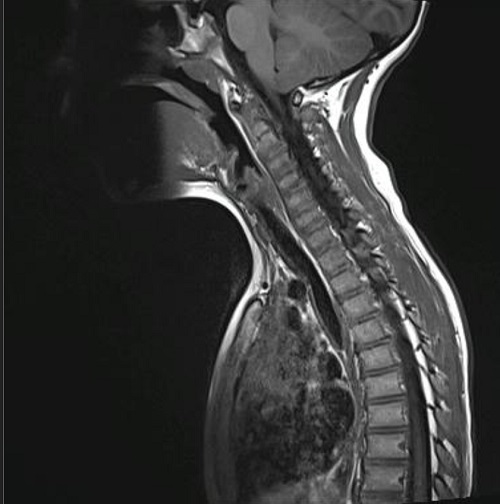

Dos meses después de la intervención quirúrgica, por algias en región dorsal, se realiza tomografía por emisión de positrones (PET/TAC) donde se aprecian las 2 lesiones ya conocidas en hueso parietal izquierdo y se detecta un foco hipermetabólico con gran intensidad de captación en lesión lítica situada en hemicuerpo izquierdo de D6. No se encuentran otros hallazgos en el resto del esqueleto ni en partes blandas, vísceras o ganglios linfáticos. La RMN confirma el hallazgo y se aprecia una lesión en D6, inespecífica, osteolítica, con algunos focos de esclerosis periféricos, compatible con hemangioma vertebral sin poder descartar GE en el contexto del paciente. La presencia de edema óseo perilesional iría a favor de GE (Figura 4).

Figura 4. Resonancia magnética nuclear

El Servicio de Hemato-Oncología del hospital de referencia, junto con los padres, decide iniciar tratamiento con indometacina, a 2 mg/kg/día. Desde entonces, el paciente se mantiene asintomático y en los controles de imagen periódicos se va notando reducción de las lesiones. Diecinueve meses después del inicio del tratamiento realizan nueva RMN que muestra ausencia de resto o recidiva de su patología de base: defecto óseo parietal izquierdo ya conocido y estable. Práctica resolución de la lesión en la vertiente izquierda del cuerpo de D6 (Figura 5). Ante estos hallazgos se decide retirar el tratamiento, permaneciendo asintomático cuatro meses después de la suspensión del mismo.

Figura 5. Resonancia magnética nuclear vertebral